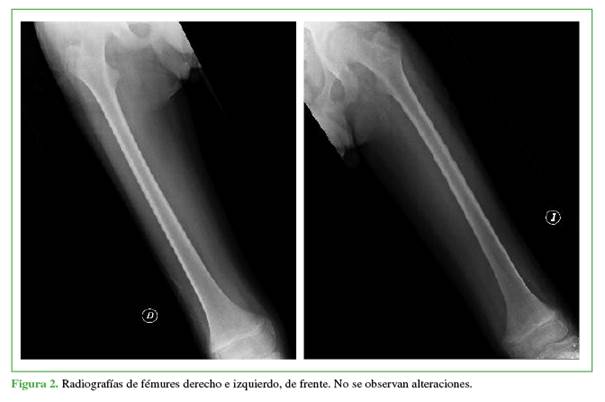

En el examen físico, el estado general era regular, tenía palidez cutánea y de mucosas generalizada; miembros inferiores simétricos, edemas grado 2 (depresión hasta 4 mm y desaparición en 15 min), abundantes petequias y hematomas de diferentes estadios evolutivos, movilidad de miembros inferiores levemente dolorosa, articulaciones móviles sin signos de flogosis, marcada debilidad muscular. El examen neurológico fue acorde a su edad; signo de Romberg negativo, fuerza 3/5 bilateral, marcha con aumento del polígono de sustentación, lograba dificultosamente la bipedestación con asistencia. Los análisis bioquímicos al ingresar arrojaron los siguientes resultados: anemia normocítica e hipocrómica (hematocrito 23%; hemoglobina 7,5 g/dl; leucocitos 5,50 mil./mm3; volumen corpuscular medio 75,4 fl; hemoglobina corpuscular media 24,6 pg; recuento plaquetario 306 mil./mm3; proteína C reactiva 0,8 mg/l). Se tomaron radiografías de huesos largos, de frente (Figuras 1 y 2).